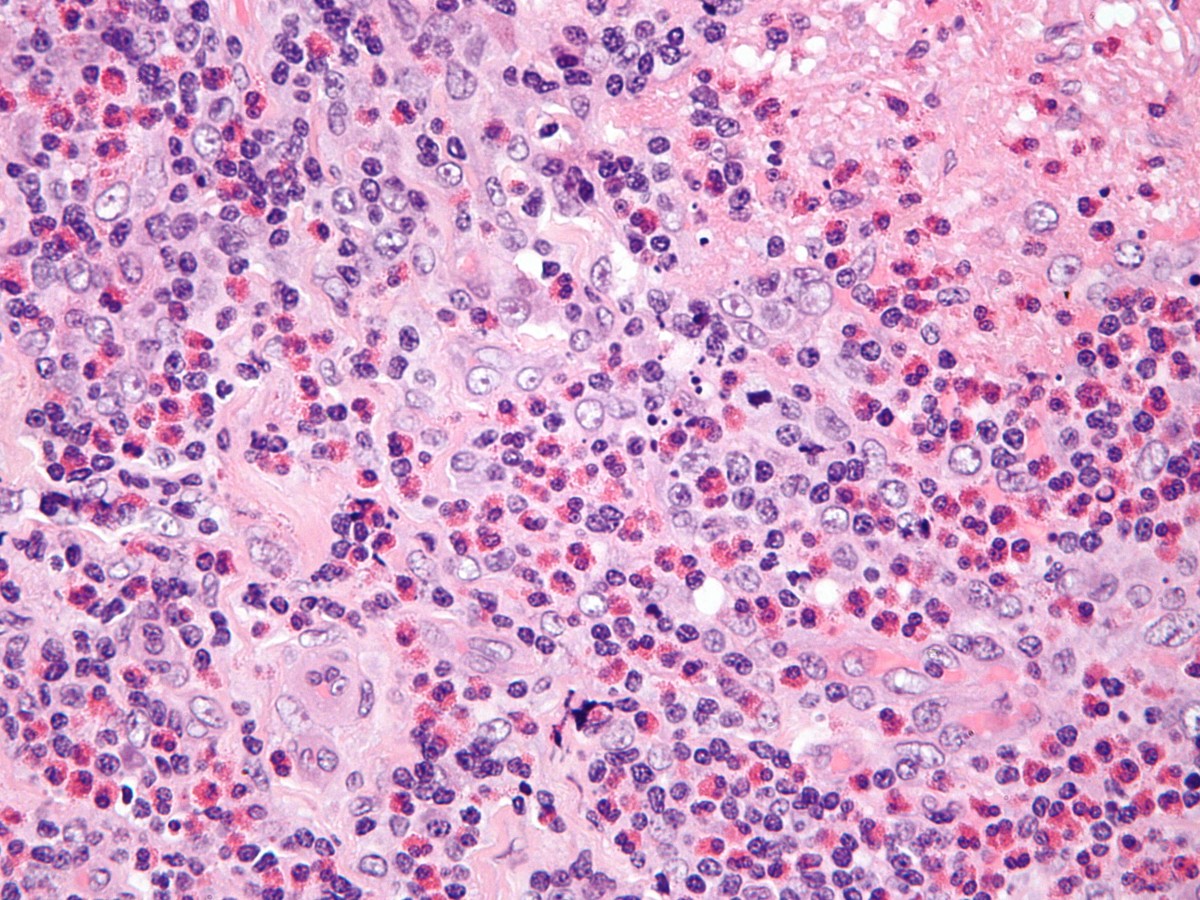

Histologie:Histologisch ziet men verspreid over het

hele preparaat lymfoïde infiltraten met een kiemcentrum, en veel eosinofielen.

Tevens een proliferatie van endotheelweefsel met dikwandige vaten en hobnail

endotheelcellen (zie ook onder

hobnail

hemangioom). Het infiltraat is polymorf en niet klonaal.

![Kimura's disease (click on photo to enlarge) [source: Michael Bonert (Nephron) - Wikimedia - Creative Commons License 3.0] Kimura's disease](../../../images/kimura-disease-2z.jpg) |

![Kimura's disease (click on photo to enlarge) [source: Michael Bonert (Nephron) - Wikimedia - Creative Commons License 3.0] Kimura's disease](../../../images/kimura-disease-3z.jpg) |

| Kimura's

disease (PA) |

Kimura's

PA foto's: Michael Bonert (Nephron) - Wikimedia (Creative Commons License

3.0)